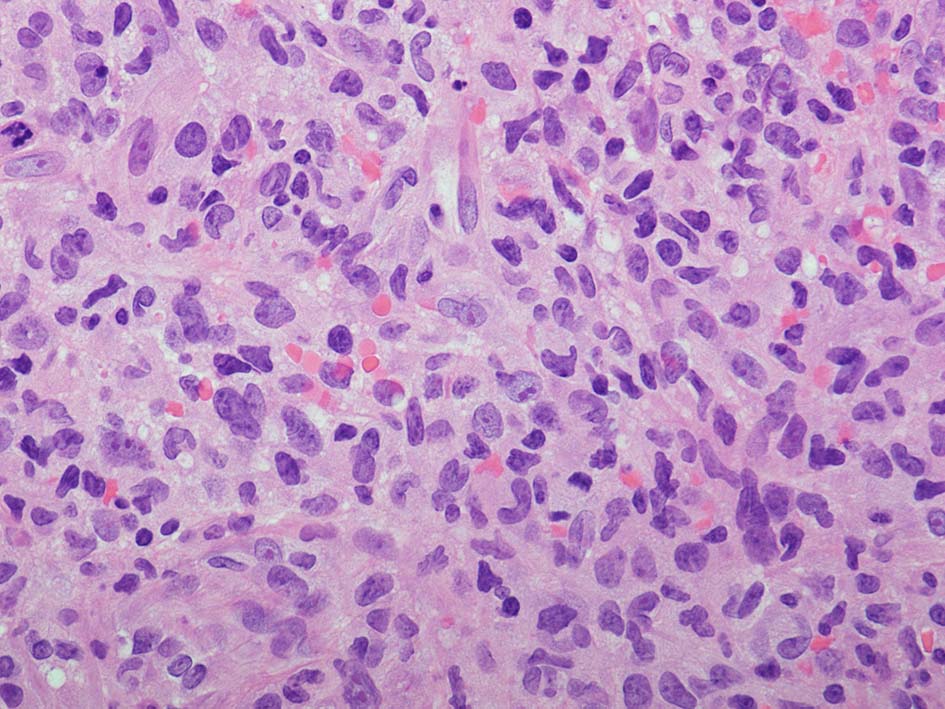

loupe像:表面に痂皮形成. 均等な組織像で,壊死や出血はみられない. 低倍ではspindle cellの密な増殖があるように見える. 拡大所見では, 類円形, 卵円形, ねじれた桿状の核, くびれ,勾玉様の核など不整形な核をもつ細胞が増殖している. クロマチンは繊細な傾向で, 核小体を1個もつ核が認められる. 高倍率10視野で 1-2個の核分裂像が数えられた.

CD20, PAX5, CD3, CD5 リンパ球マーカは陰性. Dendritic cell marker (CD1a, CD123, Langerin, etc)は陰性. S-100, CD168, CD68(KP-1)が陽性. 組織球増殖病変と考えられた. foamy macrophageやgiant cellsはほとんど認められない. 高異型度, 多型細胞の出現はないが, MIB-1 LIが高く, mitosisも増加している, 悪性の心配あり, 治療方針の決定のため consultationを行った.